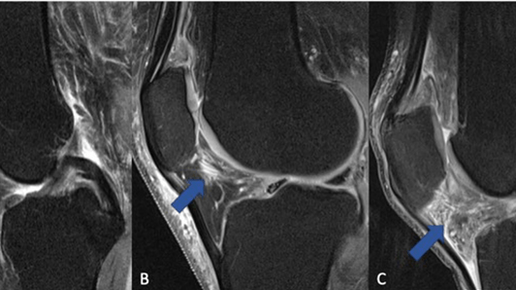

Авторы нового исследования заявили, что прием противовоспалительных обезболивающих средств, таких как ибупрофен и напроксен, при остеоартрите (артрозе) может со временем усилить воспаление в коленном суставе. Результаты исследования представлены на ежегодной конференции Радиологического общества Северной Америки (RSNA). Артроз и противовоспалительные средства Артроз является наиболее распространенной формой артрита, поражающей более 500 миллионов человек по всему миру. Чаще всего заболевание поражает суставы кисти, тазобедренные и коленные суставы...

Гонартроз

Артроз, он же остеоартроз, он же остеоартрит (в международной классификации болезней osteoarthritis) — это заболевание, связанное с износом суставного хряща и затрагивающее субхондральную кость, то есть кость, которая подлежит хрящу. Именно этот термин я описывал раньше в книге под названием «хондромаляция». Это так называемый ранний артроз. Хрящевая ткань имеет очень сложную структуру, в которой клетки хряща — хондроциты — расположены во внеклеточном матриксе, созданном из переплетений волокон длинных белков — коллагена и эластина, который эти самые хондроциты и производят...